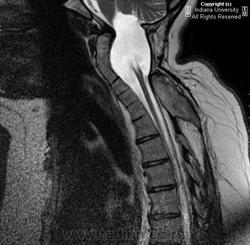

Диастематомиемия.

Наблюдение доктора Gagandeep Choudhary

"НЕЙРОРАДИОЛОГИЯ В СЕТИ". Диастематомиемия шейного отдела.

В обоих случаях перегородка имеет переднезаднее направление, но может располагаться не строго в сагиттальной плоскости и не всегда делит спинной мозг на равные части. У многих пациентов имеется выраженная асимметрия развития половин спинного мозга, вплоть до гипоплазии одной из них. Перегородка может располагаться в любом отделе позвоночника. Чаще она встречается в поясничном отделе на уровне L2-L4 сегментов, реже - в грудном, еще реже - в шейном (в последнем случае практически всегда сочетается с синдромом Клипеля – Фейля). Формирование двух и более перегородок в разных отделах позвоночника наблюдается очень редко.